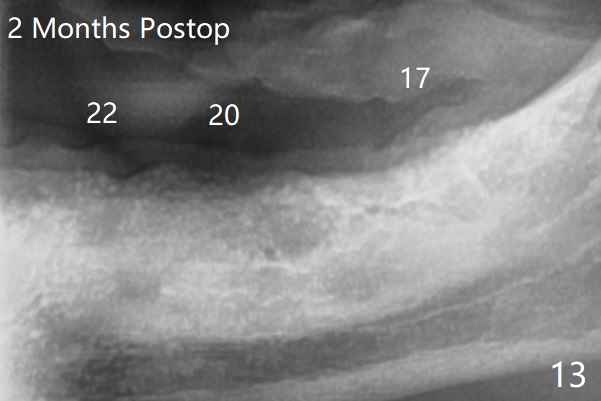

A 84-year-old man (uncontrolled diabetes) requests extraction of terminal teeth (#17, 20-22) for complete denture (Fig.1-3). He does not have finance for implants now. After extraction and debridement, 1 cc of Bond Apatite is applied to the sockets (Fig.4-6). The sockets at #20-22 are primarily closed with 4-0 PGA (Fig.7), while that of #17 with 4-0 Chromic gut suture over Osteogen Plug (a type of Collagen Plug, Fig.8). PGA sutures remain in place (Fig.9,10), while Chromic Gut ones dissolve 7 days postop (Fig.11). The ridge at the extraction sites remains robust 2 months postop (Fig.12). The sockets seem to remain radiopaque 2 months postop (Fig.13).